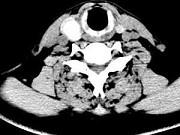

问题 男,43岁,右颈部扪及一包块,CT如图所示,应诊断为()

选项 A.甲状腺腺瘤 B.甲状腺腺癌 C.结节性甲状腺肿 D.甲状腺原发淋巴瘤 E.甲状腺转移瘤

答案 A